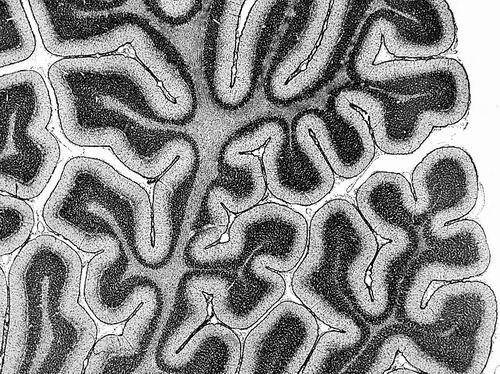

随着人的成长,大脑中协同工作的区域会发生变化。图片来源:Microscape

科学家绘制出首份关于大脑活动关键模式的图谱,并确定了这些模式在人类整个生命周期中的变化规律。3月25日,相关研究成果发表于《自然》。

这份图谱基于近3600人的脑部扫描数据,年龄跨度从婴儿到百岁老人。它映射了一种名为“功能连接”的特性,描述了不同脑区之间的协调水平。数据表明,在年轻人中,这种连接的特定模式与认知表现有关。

大脑是一个“吵闹”的地方。有时两个相距甚远的大脑区域会同时活跃,表明它们在协同工作以支持相同的功能。这些区域被认为是“功能性连接的”,尽管它们在大脑中未必相邻。

论文作者、美国北卡罗来纳大学教堂山分校的Patrick Taylor解释说,为理解这种功能性连接是如何组织的,研究人员会根据它们与大脑其他部分的连接模式,将大脑区域沿着一个比例或轴线绘制出来。这里有3个主要的功能轴。例如,感官-联想轴使研究人员能够描述沿该轴分布的脑区——从主要专注于处理感官信息的区域到参与复杂过程的区域。轴上各点的脑区具有相似的连接模式。

感官-联想轴的一端是与感官处理密切相关且与其他具有相同功能的区域相连的脑区。而轴的另一端则是支持更高层次信息处理并与众多其他区域相连的脑区。位于轴中间的是充当过渡地带的脑区,将感官处理与更抽象的思维联系起来。这意味着这些区域在功能上既与感官网络相连,又与参与复杂思维的区域相接。

从婴儿期到老年期,每个轴都遵循各自的发育路径。例如,感官-联想轴两端区域的连接性差异在儿童期和青少年期变得更加明显,并在19岁达到峰值。Taylor指出,这种分化促使年轻大脑向更成人化的组织结构发展。

研究人员还发现,那些感官-联想轴模式与人群平均水平高度吻合的年轻人,在认知表现、信息处理速度和记忆力方面均优于那些与平均水平差异较大的年轻人。